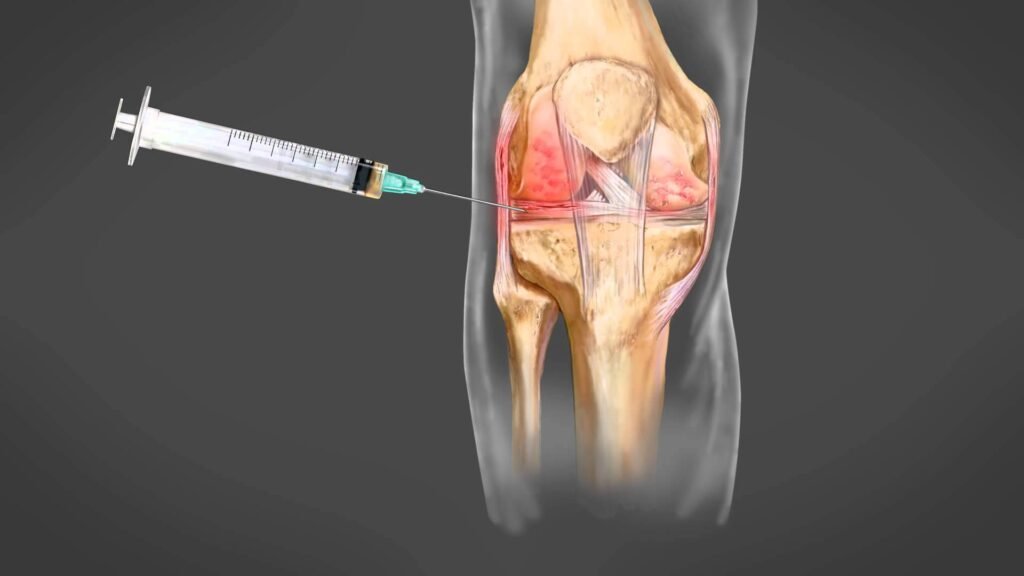

Ύστερα θα γίνει η λήψη μόνο του πλάσματος πλούσιο σε αιμοπετάλια (περίπου 4 ml) και θα γίνει τοπική έγχυση στην πάσχουσα περιοχή υπό αυστηρά αποστειρωμένες συνθήκες.

Σε ποιες περιπτώσεις μπορεί να χρησιμοποιηθεί η θεραπεία PRP;Η θεραπεία prp μπορεί να γίνει στις παρακάτω ορθοπαιδικές παθήσεις:

🔹 Χονδροπάθειες γόνατος, ισχίου, ώμου και ποδοκνημικής

🔹 Αρχόμενες οστεοαρθρίτιδες

🔹 Μερική ρήξη συνδέσμων (διαστρέμματα)